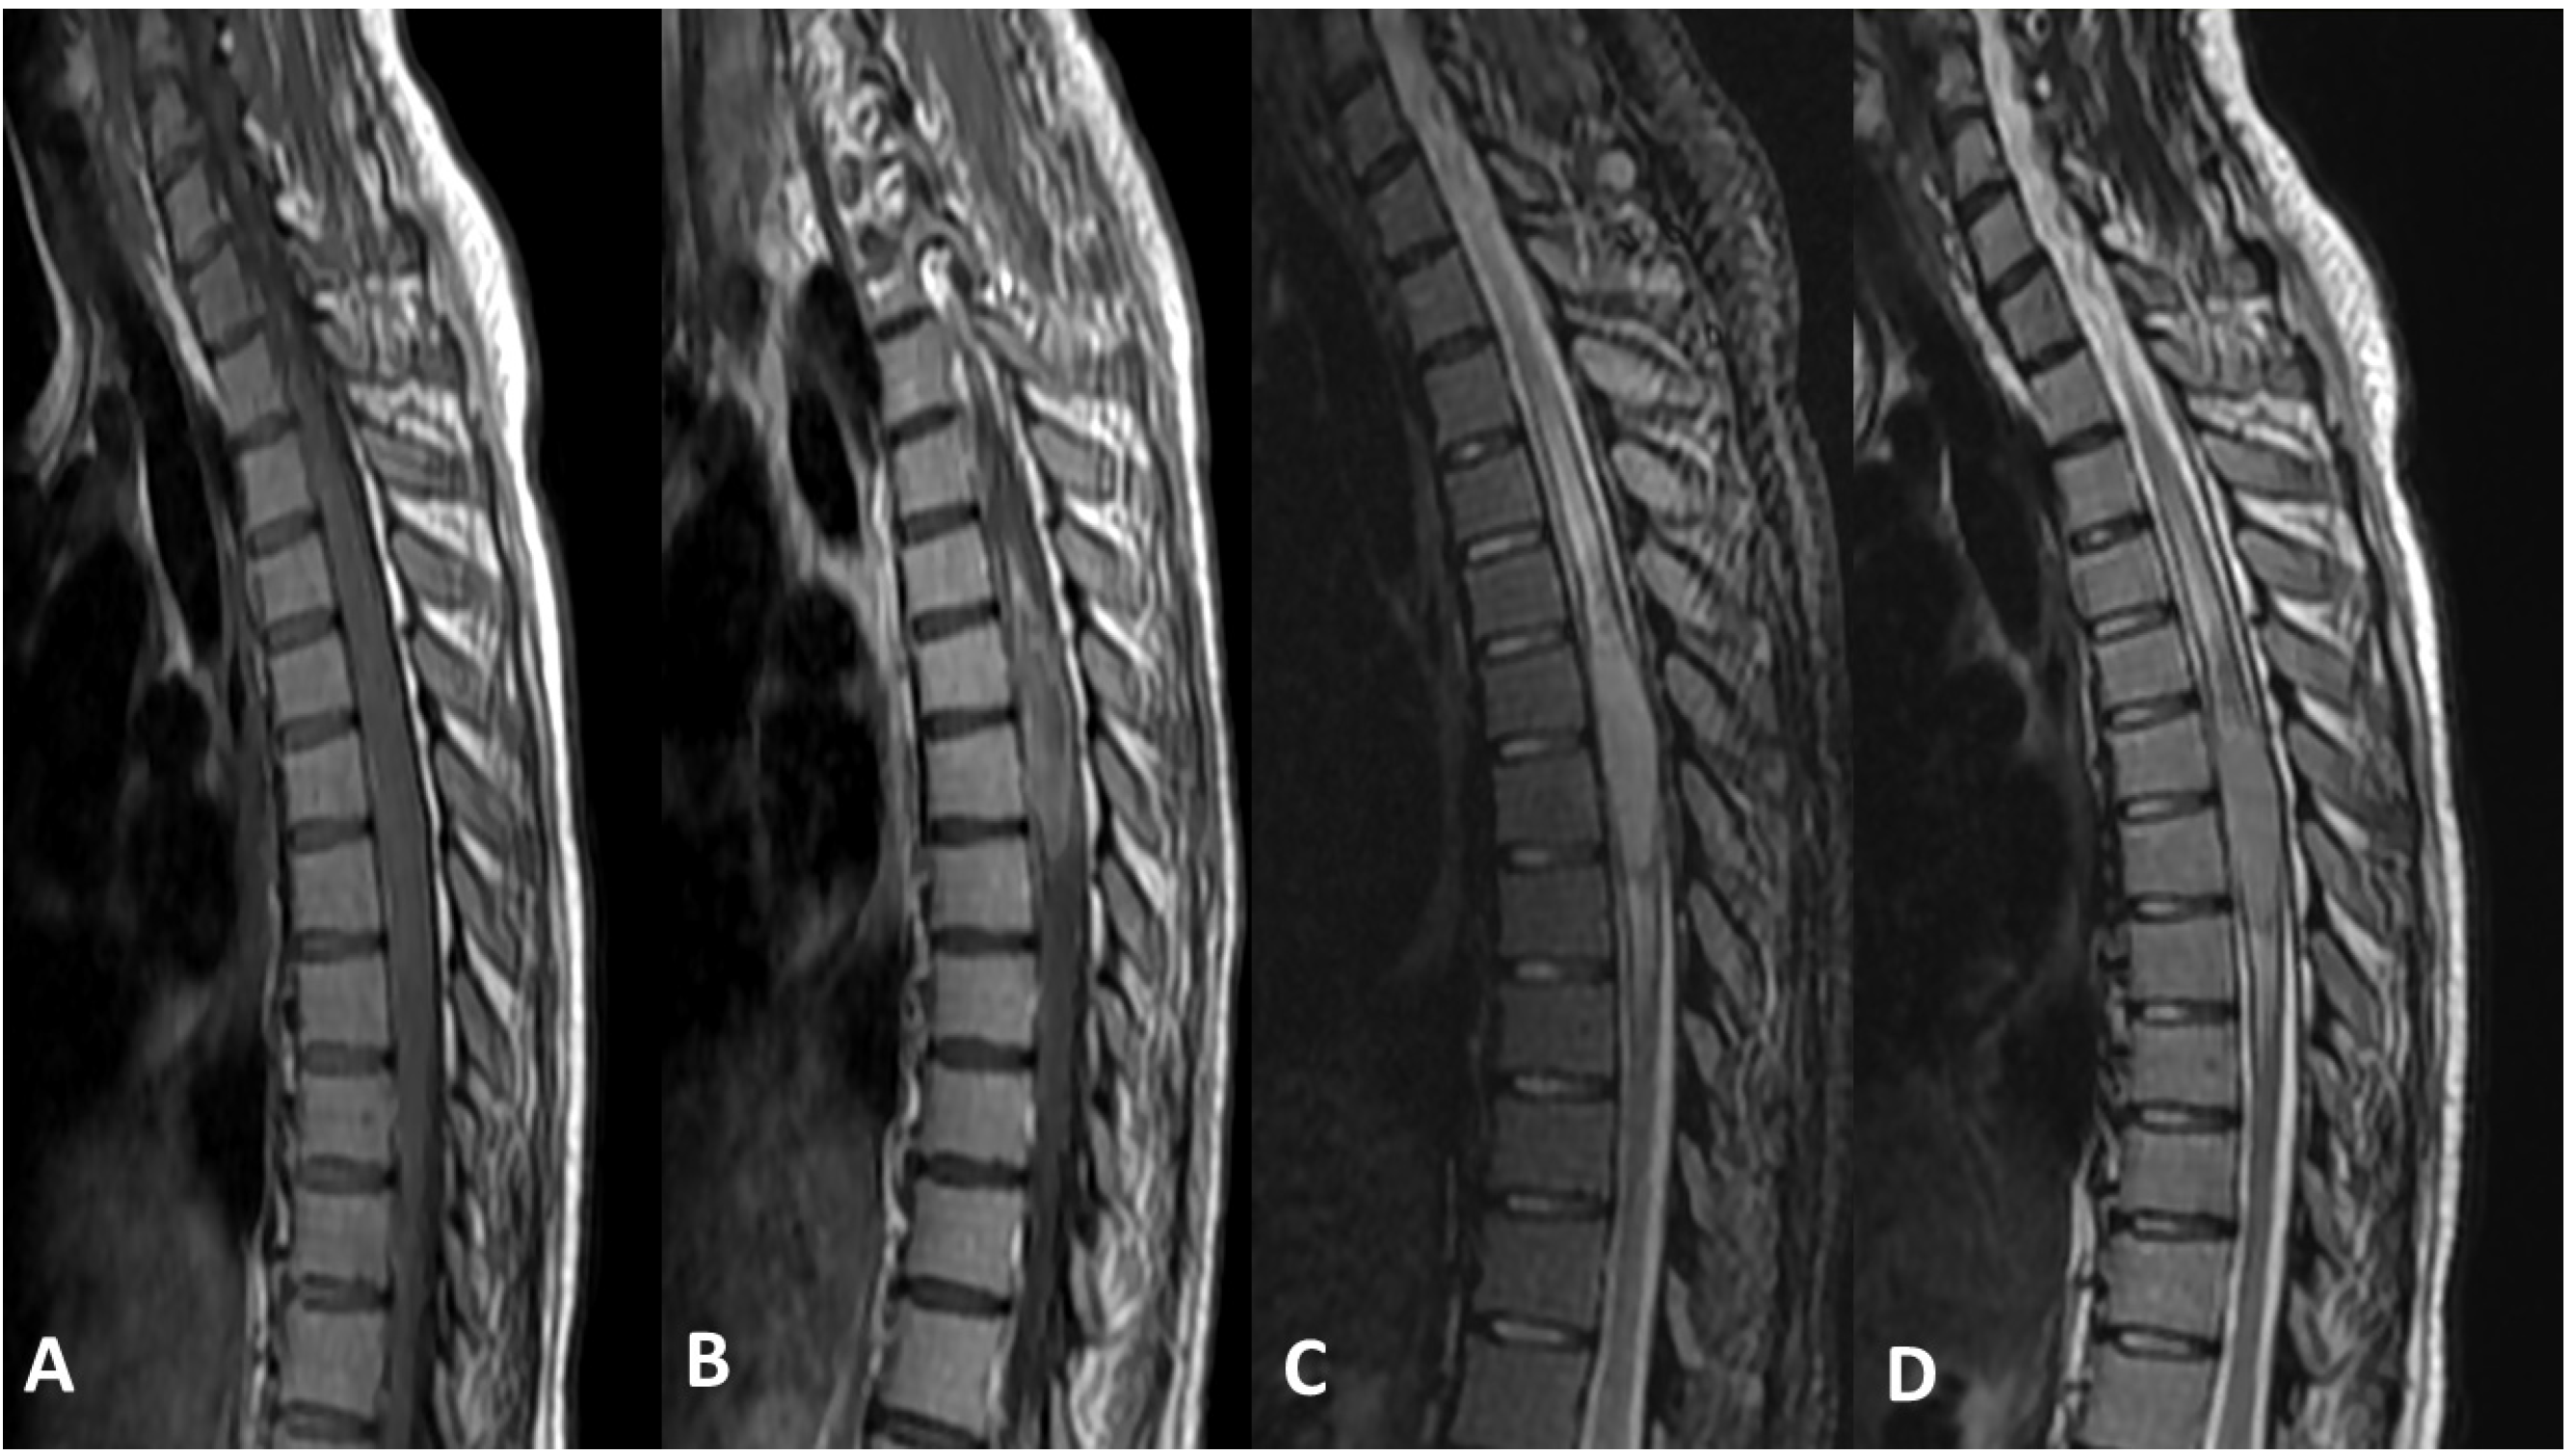

Figure 4 demonstrates an example of DMG arising from the spinal cord. There is an intramedullary mass lesion in the mid-dorsal spinal cord. The mass is expansile, showing almost isointense signal on T1 and T2-weighted sequences and mild STIR hyperintense signal with heterogeneous post contrast enhancement. The mass extends for almost four vertebral levels craniocaudally, with moderate cord edema proximal and distal to the lesion.

Figure 4.

(A) Sagittal T1-weighted pre-IV contrast sequence of the dorsal spine. (B) Sagittal T1-weighted post IV contrast sequence of the dorsal spine. (C) Sagittal STIR sequence of the dorsal spine. (D) SagittalT2-weighted sequence of the dorsal spine.